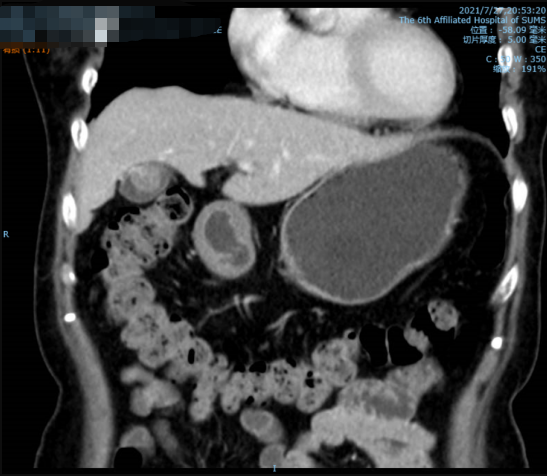

患者住院后,我们给患者复查了肿瘤指标、肝功能指标等,未见异常,增强CT仍提示胆囊癌可能性大,并胆囊多发结石。我们科室讨论后认为根据目前的资料仍无法确定100%就是胆囊癌,但手术需要恶性肿瘤的标准进行。按计划行“腹腔镜胆囊切除+局部肝切除+区域淋巴结清扫”。术后恢复顺利,术后第5天即康复出院。

影像学检查提示息肉较前明显增大,伴胆囊多发结石